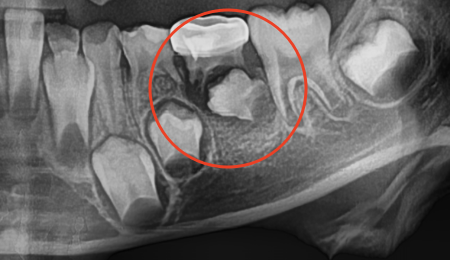

有时,六龄齿也会像智齿一样“顶在”前面的牙齿上而无法正常萌出,需要提前干预。因此,六龄齿萌出阶段也建议带孩子去医院检查一下。

划重点⚠️:六龄齿可能像智齿一样被“卡住”。

曲面断层片怎么看换牙与身高有关吗?关于孩子换牙的所有疑问一篇说清_https://www.jmylbn.com_新闻资讯_第22张

图注:六龄齿被“卡住”,无法正常萌出